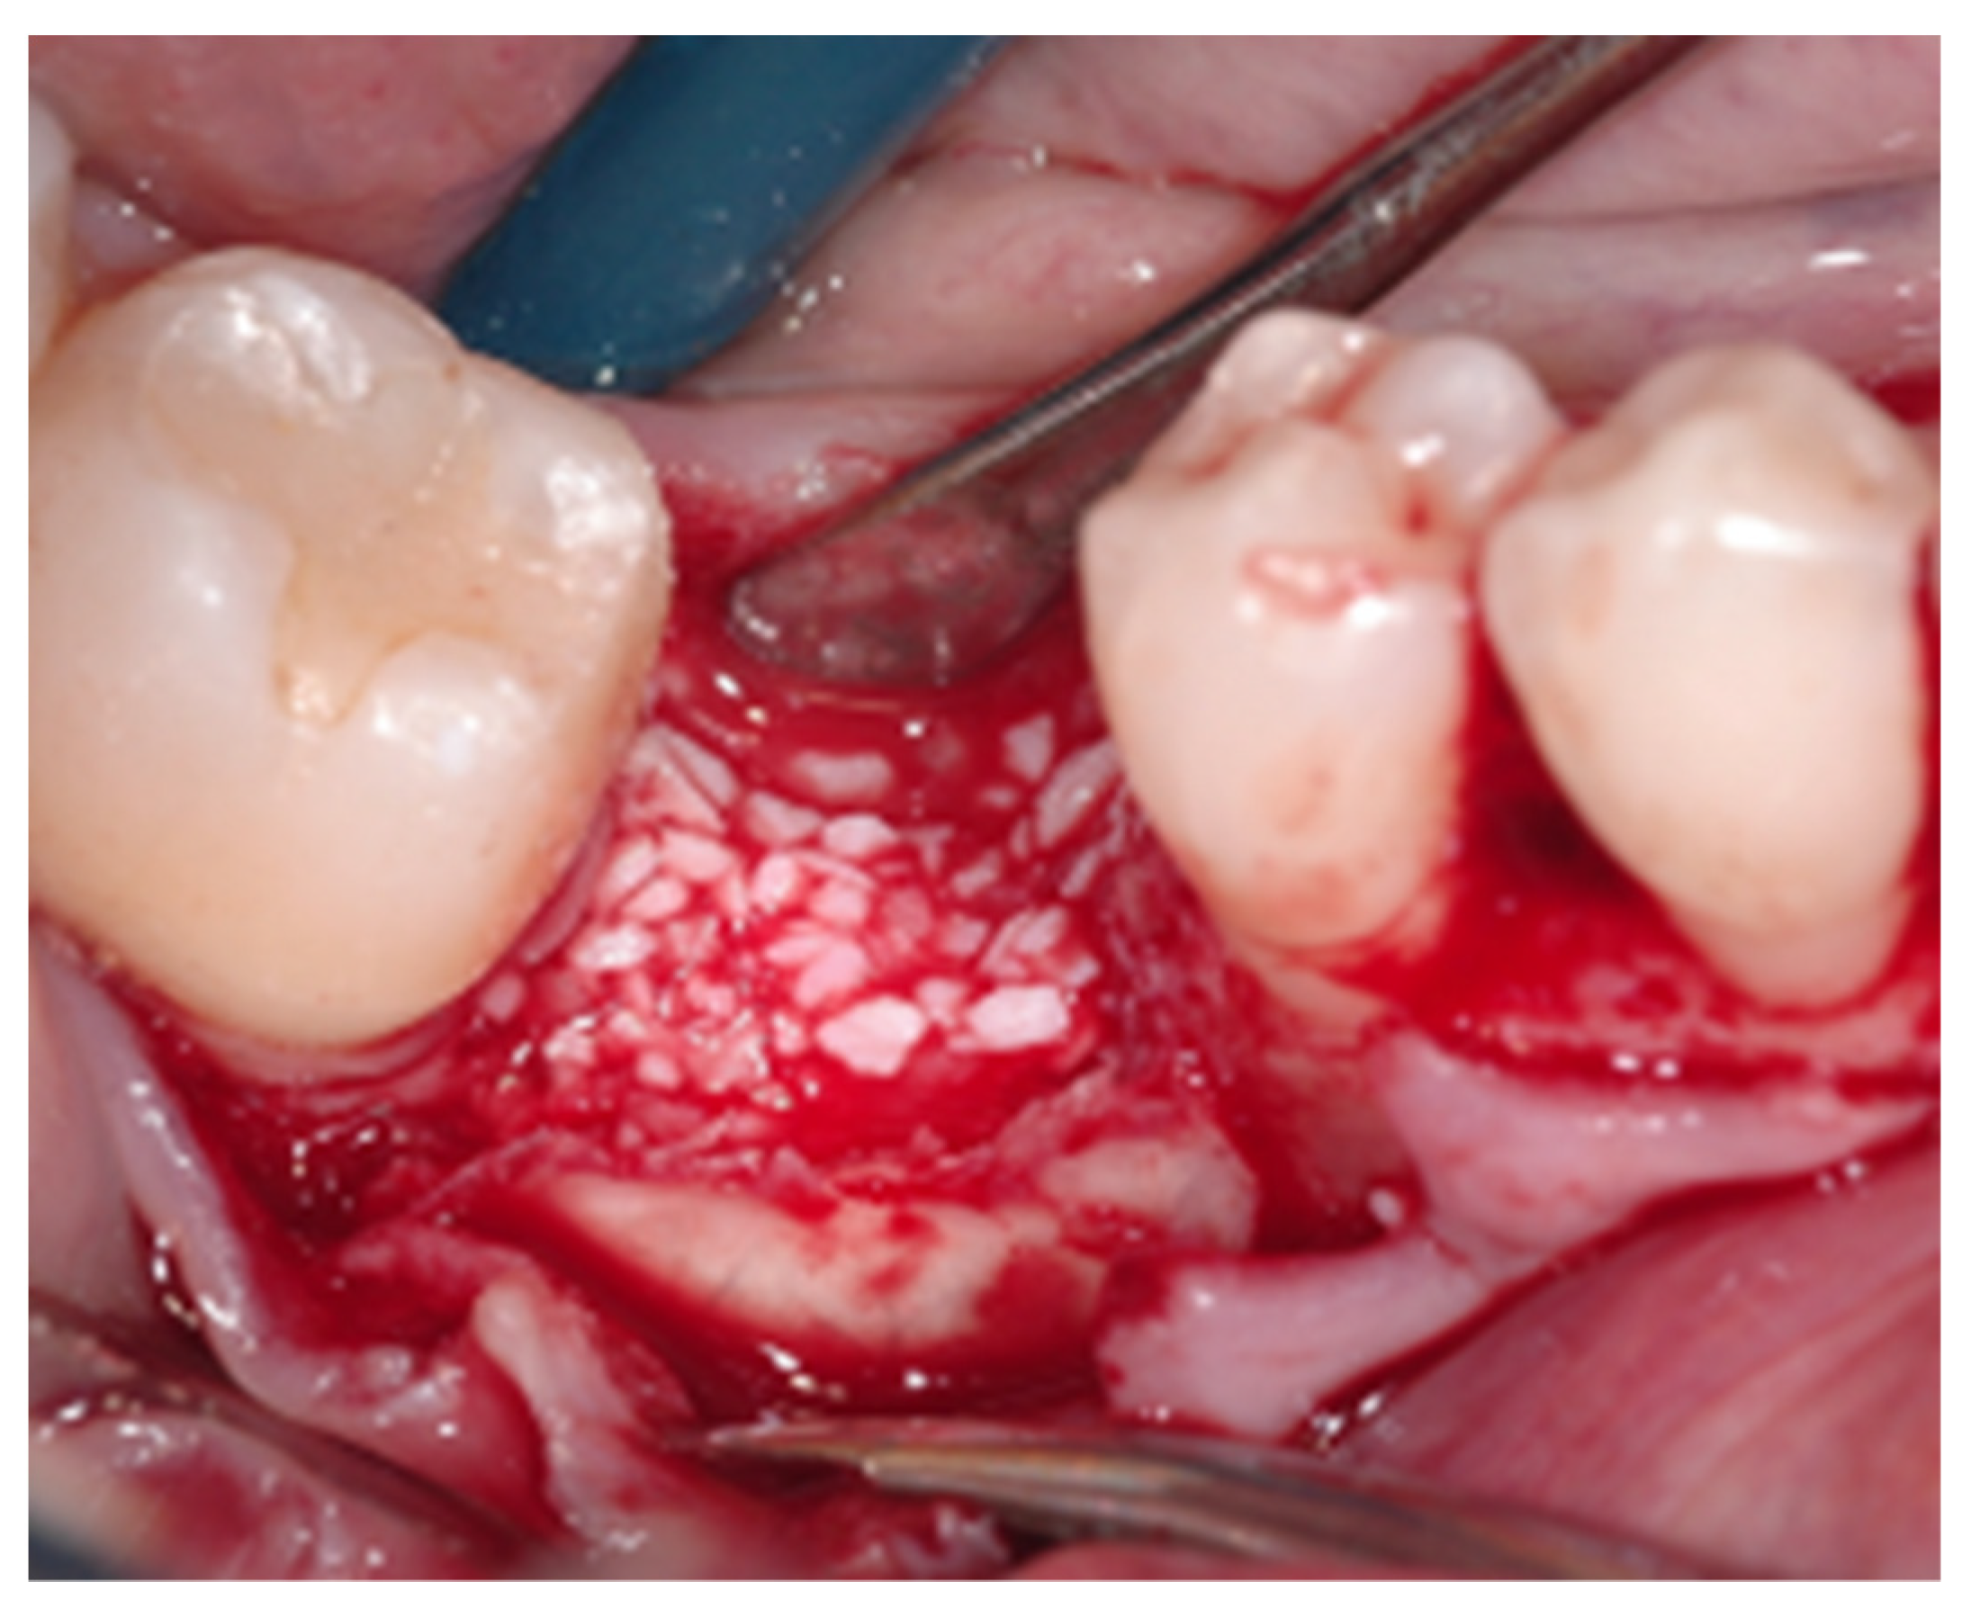

2.2. Surgical Procedure

2.4. Histologic and Histomorphometric Analysis

Histologic and Histomorphometric Results